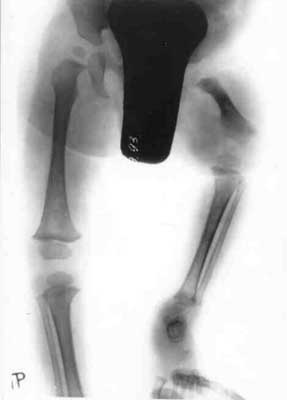

Pffd in children

Ñhildren with PFFD